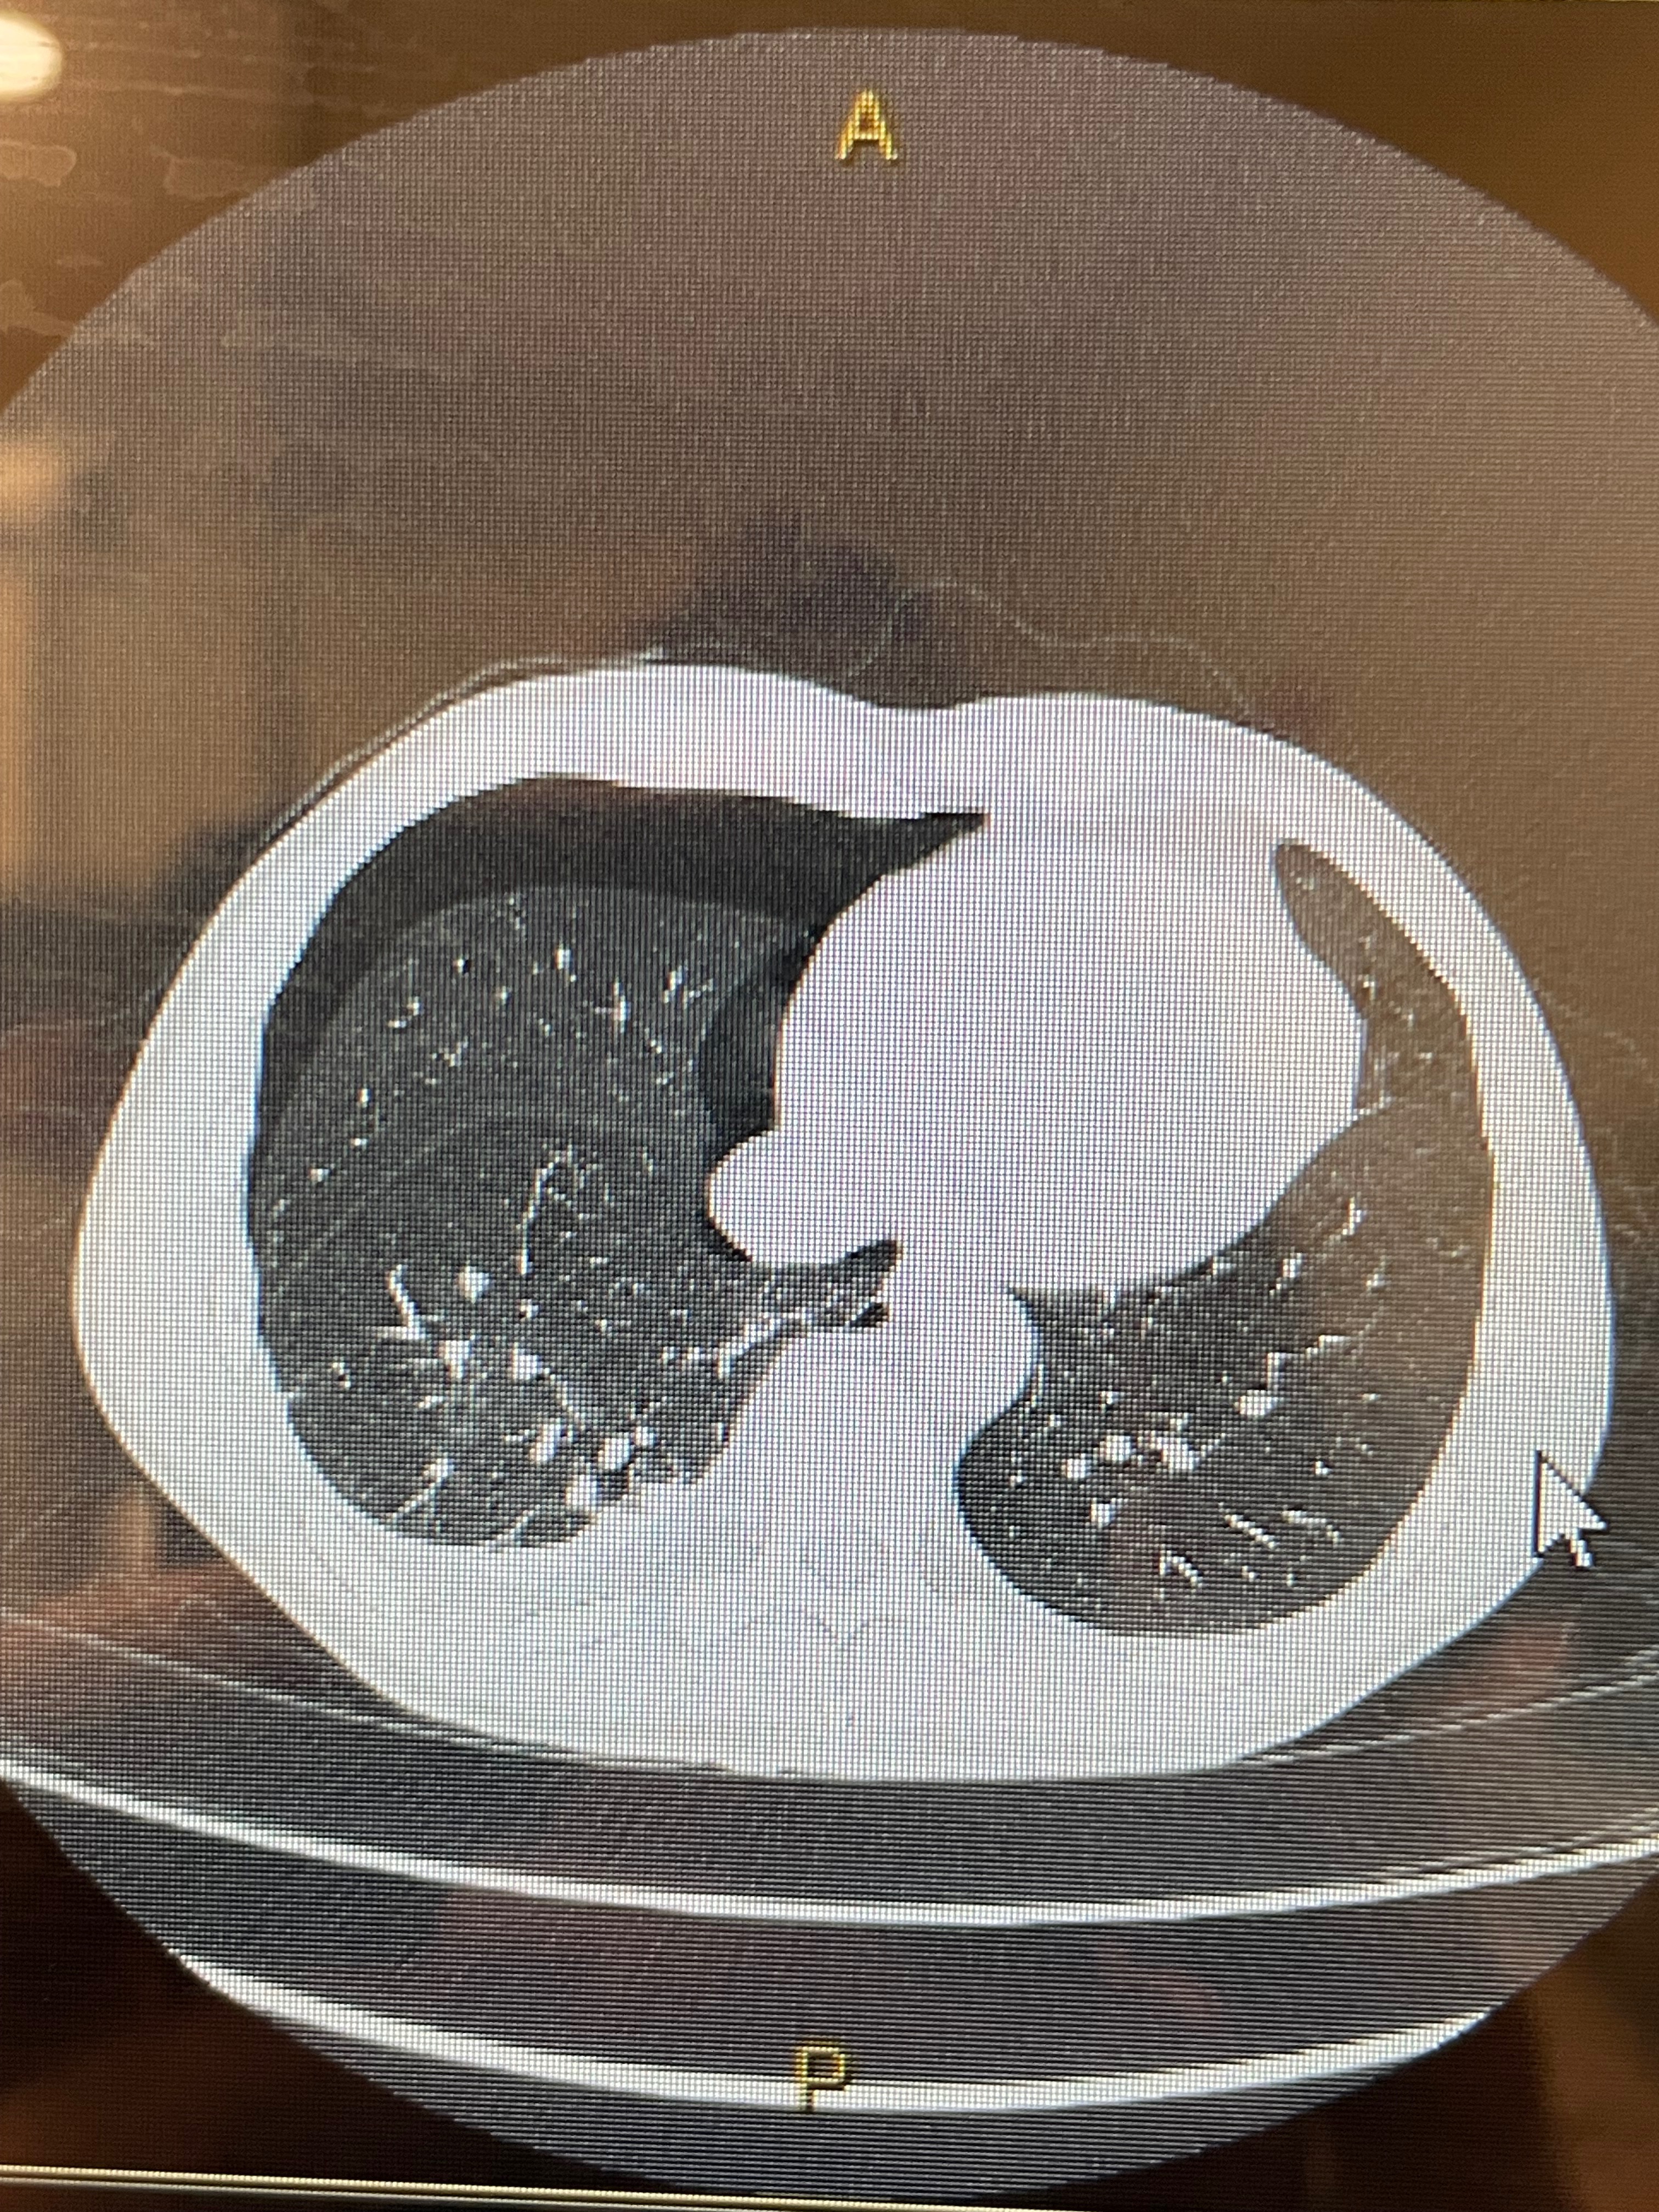

Matthew was skiing on Sunday, December 14th, when he came to a trail merge and was hit from behind. As the downhill skier, he suffered serious injuries, including six broken ribs, a saddle pulmonary embolism, deep vein thromboses, and a pneumothorax. At first, Matthew was unaware of the extent of his injuries, but a day later, he ended up in the ER. There, he received a chest tube, was started on a heparin drip, and was life-flighted from Meeker ER to St. Mary’s ER in Grand Junction for urgent care. He is currently in the ICU, with hopes of moving to a medsurge floor soon. As part of his recovery, Matthew will require blood thinners for a minimum of three months, but more likely six to twelve months, and will most likely need to use oxygen for a few weeks.